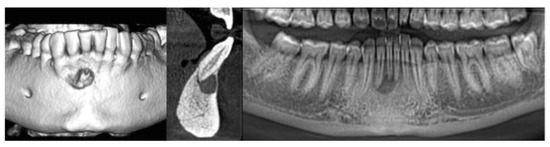

| 1 | 46 | Female | Apical Granuloma |

| 2 | 31 | Female | Periapical Cyst |

| 3 | 56 | Male | Apical Granuloma |

| 4 | 49 | Male | Apical Granuloma |

| 5 | 27 | Male | Periapical Cyst |

| 6 | 52 | Female | Periapical Cyst |

| 7 | 48 | Male | Apical Granuloma |

| 8 | 61 | Male | Periapical Cyst |

| 9 | 43 | Female | Apical Granuloma |

| 10 | 39 | Male | Apical Granuloma |

| IMAGE QUALITY EVALUATION SCORES | |

| Endodontist I | 7 |

| Endodontist II | 6 |

| Endodontist III | 7 |

| Endodontist IV | 8 |

| Endodontist V | 7 |

| MEAN VALUE | 7.0 |